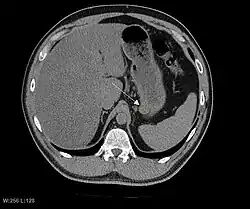

CT scanning is often undertaken (see the radiology section).

The purpose of radiologic imaging is to locate the lesion, evaluate for signs of invasion and detect metastasis. Features of GIST vary depending on tumor size and organ of origin. The diameter can range from a few millimeters to more than 30 cm. Larger tumors usually cause symptoms in contrast to those found incidentally which tend to be smaller and have better prognosis.[4][20] Large tumors tend to exhibit malignant behavior but small GISTs may also demonstrate clinically aggressive behavior.[21]

Barium fluoroscopic examinations and CT are commonly used to evaluate the patient with abdominal complaints. Barium swallow images show abnormalities in 80% of GIST cases.[21] However, some GISTs may be located entirely outside the lumen of the bowel and will not be appreciated with a barium swallow. Even in cases when the barium swallow is abnormal, an MRI or CT scan must follow since it is impossible to evaluate abdominal cavities and other abdominal organs with a barium swallow alone. In a CT scan, abnormalities may be seen in 87% of patients and it should be made with both oral and intravenous contrast.[21] Among imaging studies, MRI has the best tissue contrast, which aids in the identification of masses within the GI tract (intramural masses). Intravenous contrast material is needed to evaluate lesion vascularity.

Preferred imaging modalities in the evaluation of GISTs are CT and MRI,[23]: 20–21 and, in selected situations, endoscopic ultrasound. CT advantages include its ability to demonstrate evidence of nearby organ invasion, ascites, and metastases. The ability of an MRI to produce images in multiple planes is helpful in determining the bowel as the organ of origin (which is difficult when the tumor is very large), facilitating diagnosis.

Since GISTs arise from the bowel layer called muscularis propria (which is deeper to the mucosa and submucosa from a luminal perspective), small GIST imaging usually suggest a submucosal process or a mass within the bowel wall. In barium swallow studies, these GISTs most commonly present with smooth borders forming right or obtuse angles with the nearby bowel wall, as seen with any other intramural mass. The mucosal surface is usually intact except for areas of ulceration, which are generally present in 50% of GISTs. Ulcerations fill with barium causing a bull's eye or target lesion appearance. In contrast-enhanced CT, small GISTs are seen as smooth, sharply defined intramural masses with homogeneous attenuation.

As the tumor grows it may project outside the bowel (exophytic growth) and/or inside the bowel (intraluminal growth), but they most commonly grow exophytically such that the bulk of the tumor projects into the abdominal cavity. If the tumor outstrips its blood supply, it can necrose internally, creating a central fluid-filled cavity with bleeding and cavitations that can eventually ulcerate and communicate into the lumen of the bowel. In that case, barium swallow may show an air, air-fluid levels or oral contrast media accumulation within these areas.[21][25] Mucosal ulcerations may also be present. In contrast-enhanced CT images, large GISTs appear as heterogeneous masses due to areas of living tumor cells surrounding bleeding, necrosis or cysts, which is radiographically seen as a peripheral enhancement pattern with a low attenuation center.[20] In MRI studies, the degree of necrosis and bleeding affects the signal intensity pattern. Areas of bleeding within the tumor will vary its signal intensity depending on how long ago the bleeding occurred. The solid portions of the tumor are typically low signal intensity on T1-weighted images, are high signal intensity on T2-weighted images and enhanced after administration of gadolinium. Signal-intensity voids are present if there is gas within areas of necrotic tumor.[22][26][27]

Features of malignancy

Malignancy is characterized by local invasion and metastases, usually to the liver, omentum and peritoneum. However, cases of metastases to bone, pleura, lungs and retroperitoneum have been seen. In distinction to gastric adenocarcinoma or gastric/small bowel lymphoma, malignant lymphadenopathy (swollen lymph nodes) is uncommon (<10%) and thus imaging usually shows absence of lymph node enlargement.[20] If metastases are not present, other radiologic features suggesting malignancy include: size (>5 cm), heterogeneous enhancement after contrast administration, and ulcerations.[4][20][28] Also, overtly malignant behavior (in distinction to malignant potential of lesser degree) is less commonly seen in gastric tumors, with a ratio of behaviorally benign to overtly malignant of 3-5:1.[4] Even if radiographic malignant features are present, these findings may also represent other tumors and definitive diagnosis must be made immunochemically.